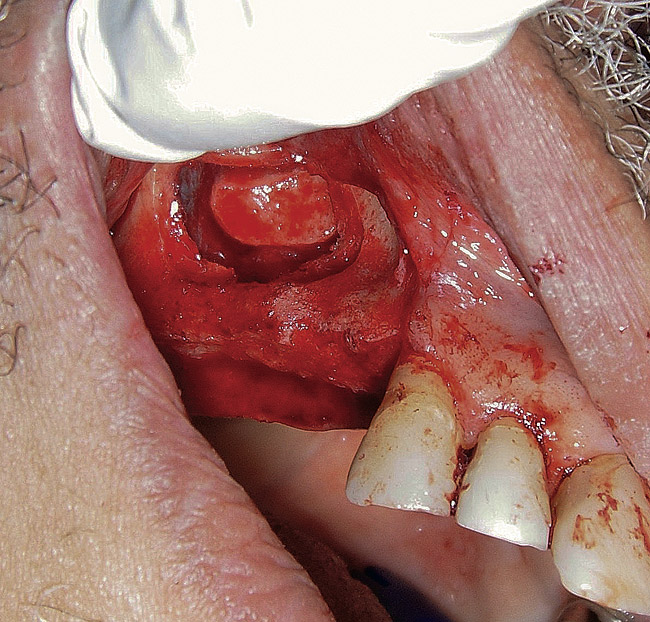

The lateral approach is also used for sinus floor elevation. It is indicated when there is reduced residual bone height, which does not allow standard implant placement or placement of implants in combination with minor sinus floor elevation using the osteotome technique (Figure 1, Figure 2 and Figure 3). Contraindications are excessive interarch distance due to unfavorable crown-to-root ratio, acute or chronic unresolved sinusitis, current sinus pathology (eg, cysts or tumors), lodged root tips in the sinus, history of heavy smoking, a systemic compromise, and psychological problems.

Figure  3   Elevation of the bony window.

Figure 3